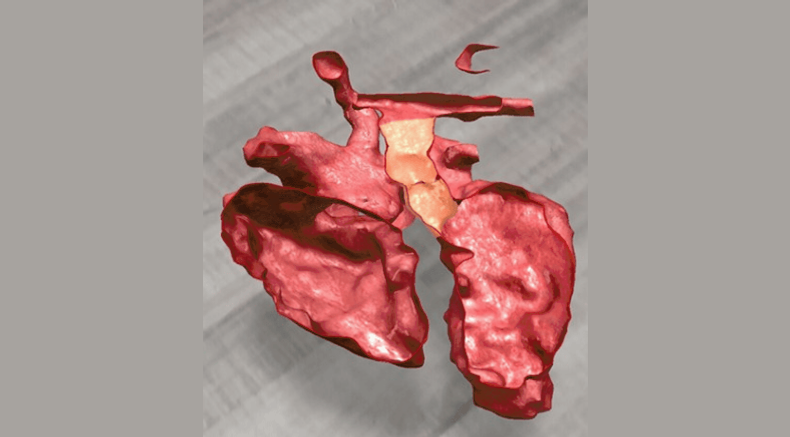

Three-dimensional virtual model of fetal heart showing transposition of the great arteries

Leite, M.d.F.P., Bravo-Valenzuela, N.J., Araujo Júnior, E., Ribeiro, G., Arcoverde, V. and Werner, H. (2025), Transposition of the great arteries: three-dimensional virtual navigation inside the fetal heart. Ultrasound Obstet Gynecol, 66: 669-671. https://doi.org/10.1002/uog.70032

Virtual rendering of fetal heart with transposition of the great arteries with cardiac structures segmented by colour for the purpose of virtual navigation

Leite, M.d.F.P., Bravo-Valenzuela, N.J., Araujo Júnior, E., Ribeiro, G., Arcoverde, V. and Werner, H. (2025), Transposition of the great arteries: three-dimensional virtual navigation inside the fetal heart. Ultrasound Obstet Gynecol, 66: 669-671.